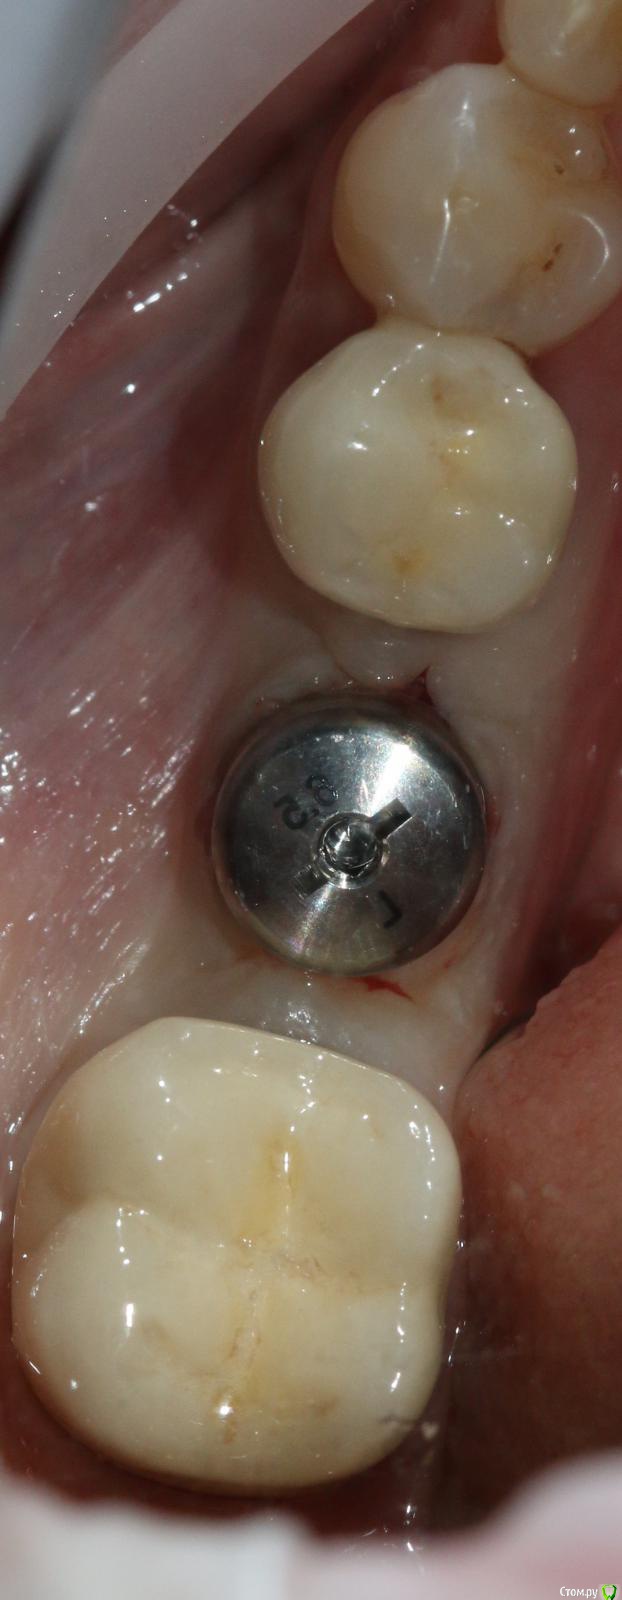

Ильдар Опубликовано 29 марта, 2015 Поделиться Опубликовано 29 марта, 2015 Коллеги, здравствуйте!Вот демонтировал старье. мк на зубы.имплант 4310, поставил поглубже.мк на имплант - техник прислал коронку с шахтой и абатмент,я склеил на fuji1. закрутил на 35 н.залепил не очень красиво , но с плавиковой, силаном и олбонд 3. думаю надежно.контрольный прицельный есть, видимо забыл его. извиняюсь за нечеткие fото. буду рад отзывам 3 Ссылка на комментарий

Ильдар Опубликовано 29 марта, 2015 Автор Поделиться Опубликовано 29 марта, 2015 чет не понятно у вас винтовая или цементная фиксация? техник начинал делать цементную. после литья каркаса я его попросил модиицировать под винтовую. он сделал отверстие в коронке, облицевал, заполировал. я склеил абатмент и коронку в руках, закрутил в рот. Ссылка на комментарий

bugel Опубликовано 30 марта, 2015 Поделиться Опубликовано 30 марта, 2015 Наверно основание абатмента глубоко под десневой части, чтобы цемента не было после фиксации- периимплантита в будущем, поэтому перевёл в винтовую. Ссылка на комментарий

Ильдар Опубликовано 30 марта, 2015 Автор Поделиться Опубликовано 30 марта, 2015 Наверно основание абатмента глубоко под десневой части, чтобы цемента не было после фиксации- периимплантита в будущем, поэтому перевёл в винтовую.Да Ссылка на комментарий

Ильдар Опубликовано 30 марта, 2015 Автор Поделиться Опубликовано 30 марта, 2015 а зачем?Видимый металл на 6-м это не абатмент, это гирлянда. Граница коронка /абатмент глубже. Поэтому винтовая. Ссылка на комментарий

АнтонТЛТ Опубликовано 30 марта, 2015 Поделиться Опубликовано 30 марта, 2015 чет не понятно у вас винтовая или цементная фиксация? SCRP screw-cement retained prosthesis (цементно-винтовая фиксация) Ссылка на комментарий